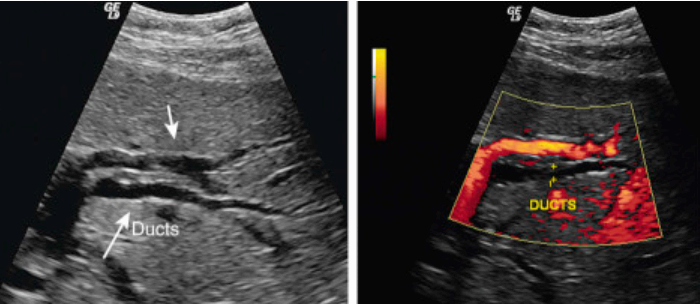

- 간내담관(intrahepatic bile duct)의 좌우직경은 2mm 이하이다. 직경이 2mm 이상이거나 portal vein 직경의 40% 이상일 때는 확장된 걸로 간주한다.

intrahepatic duct measurement (left)

intrahepatic duct measurement(right)